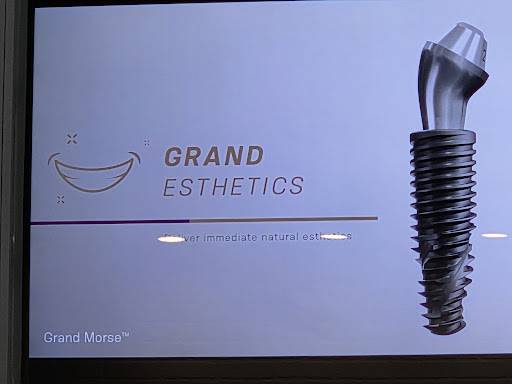

Dental Implant Restoration

Price changes 60 minutesDental implant restoration involves placing the zirconia crown screwed to the implant to restore the function and aesthetics of the tooth.Book Quick view -